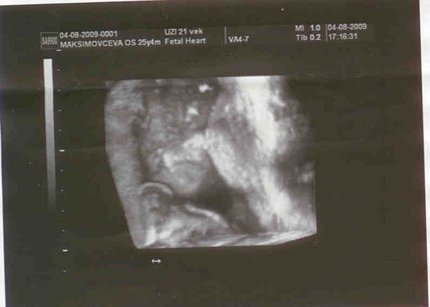

Беременность 22 недели мальчик

Беременность 22 недели мальчик 115 фото